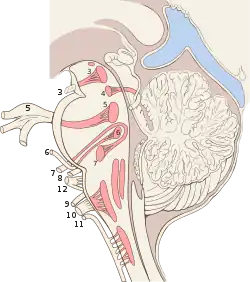

Cranial nerves have paths within and outside the skull. The paths within the skull are called "intracranial" and the paths outside the skull are called "extracranial". There are many holes in the skull called "foramina" by which the nerves can exit the skull. All cranial nerves are paired, which means they occur on both the right and left sides of the body. The muscle, skin, or additional function supplied by a nerve, on the same side of the body as the side it originates from, is an ipsilateral function. If the function is on the opposite side to the origin of the nerve, this is known as a contralateral function.[9]

Exiting the skull and extracranial course

| Location | Nerve |

|---|---|

| cribriform plate | Terminal nerve (0) |

| cribriform plate | Olfactory nerve (I) |

| optic foramen | Optic nerve (II) |

| superior orbital fissure | Oculomotor (III) Trochlear (IV) Abducens (VI) Trigeminal V1 (ophthalmic) |

| foramen rotundum | Trigeminal V2 (maxillary) |

| foramen ovale | Trigeminal V3 (mandibular) |

| stylomastoid foramen | Facial nerve (VII) |

| internal auditory canal | Vestibulocochlear (VIII) |

| jugular foramen | Glossopharyngeal (IX) Vagus (X) Accessory (XI) |

| hypoglossal canal | Hypoglossal (XII) |

After emerging from the brain, the cranial nerves travel within the skull, and some must leave it in order to reach their destinations. Often the nerves pass through holes in the skull, called foramina, as they travel to their destinations. Other nerves pass through bony canals, longer pathways enclosed by bone. These foramina and canals may contain more than one cranial nerve and may also contain blood vessels.[13]

- The terminal nerve (0), is a thin network of fibers associated with the dura and lamina terminalis running rostral to the olfactory nerve, with projections through the cribriform plate.

- The olfactory nerve (I), passes through perforations in the cribriform plate part of the ethmoid bone. The nerve fibres end in the upper nasal cavity.

- The optic nerve (II) passes through the optic foramen in the sphenoid bone as it travels to the eye.

- The oculomotor nerve (III), trochlear nerve (IV), abducens nerve (VI) and the ophthalmic branch of the trigeminal nerve (V1) travel through the cavernous sinus into the superior orbital fissure, passing out of the skull into the orbit.

- The maxillary division of the trigeminal nerve (V2) passes through foramen rotundum in the sphenoid bone.

- The mandibular division of the trigeminal nerve (V3) passes through foramen ovale of the sphenoid bone.

- The facial nerve (VII) and vestibulocochlear nerve (VIII) both enter the internal auditory canal in the temporal bone. The facial nerve then reaches the side of the face by using the stylomastoid foramen, also in the temporal bone. Its fibers then spread out to reach and control all of the muscles of facial expression. The vestibulocochlear nerve reaches the organs that control balance and hearing in the temporal bone and therefore does not reach the external surface of the skull.

- The glossopharyngeal (IX), vagus (X) and accessory nerve (XI) all leave the skull via the jugular foramen to enter the neck. The glossopharyngeal nerve provides sensation to the upper throat and the back of the tongue, the vagus supplies the muscles in the larynx and continues downward to supply parasympathetic supply to the chest and abdomen. The accessory nerve controls the trapezius and sternocleidomastoid muscles in the neck and shoulder.

- The hypoglossal nerve (XII) exits the skull using the hypoglossal canal in the occipital bone.